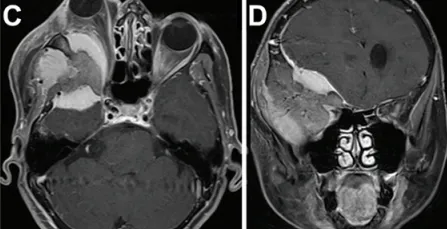

术前MRI和CT显示右侧巨大蝶骨嵴外侧脑膜瘤,伴有慢性钩回疝、脑干受压、中线移位1.4厘米及相关脑积水。术前右眼视力为20/400。患者还存在显著的右侧偏瘫及嗜睡。

术前MRI(图C)显示显著的眼球突出及视神经受压程度(眼球突出指数=2.41)。肿瘤在蝶骨眶区浸润的显著宽度(图D)。